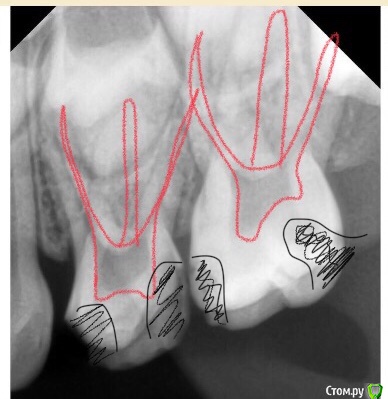

CRAZYDUCK Опубликовано 7 мая, 2018 Автор Поделиться Опубликовано 7 мая, 2018 (изменено) Лечение пульпита ; 6.4 необратимый , 6.5 обратимый .Продолжительность 1:15 час ( с момента входа в кабинет и до прощания )6.4-каналы -протейпер дентсплай Sx, ручные инструменты 25.02, гипохлорит 3,2%, пломбирование каналов Йодотин( отличный аналог метапекса , который всегда идёт из канюли в отличии от метапекса ), восстановление культи СИЦ, коронка 3М ESPE стальная .6.5 - ампутация , ХГ2%, спонтанный гемостаз , рутдент быстротвердеющий ( МТА), изоляция Calcimol, реставрация Charisma. Все лечение в одно посещение - долго для ребёнка 4 лет , но так лучше . Пришла к такому методу работы относительно недавно .Больше нравится работать таким образом - 2-3 рядом стоящих зуба в одно посещение . В этот раз было уже не до фото . Для начинающих коллег на rvg выделила полости кариозные и пульпарные полости. Изменено 7 мая, 2018 пользователем CRAZYDUCK 4 Ссылка на комментарий